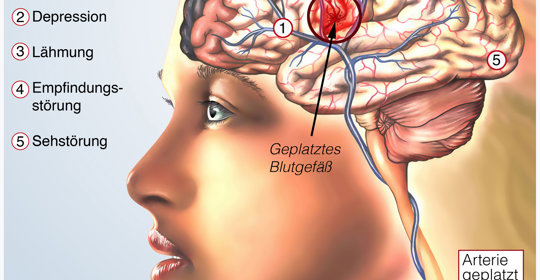

腦中風後遺症的症狀、前兆、治療和預防

腦溢血後遺症的症狀、前兆、治療和預防

腦血管破裂後遺症的症狀、前兆、治療和預防

腦動脈瘤破裂後遺症的防治與管理:症狀、前兆、治療與預防

腦梗塞後遺症的症狀、前兆、治療與預防

腦出血引流手術後遺症的症狀、前兆、治療和預防

腦缺氧後遺症的症狀表現、前兆、治療及預防